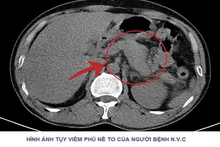

Vừa qua, Khoa Cấp cứu – Bệnh viện Đa khoa tỉnh Phú Thọ tiếp nhận người bệnh N.V.C (47 tuổi, trú tại tỉnh Phú Thọ), nhập viện trong tình trạng đau bụng dữ dội vùng thượng vị,...